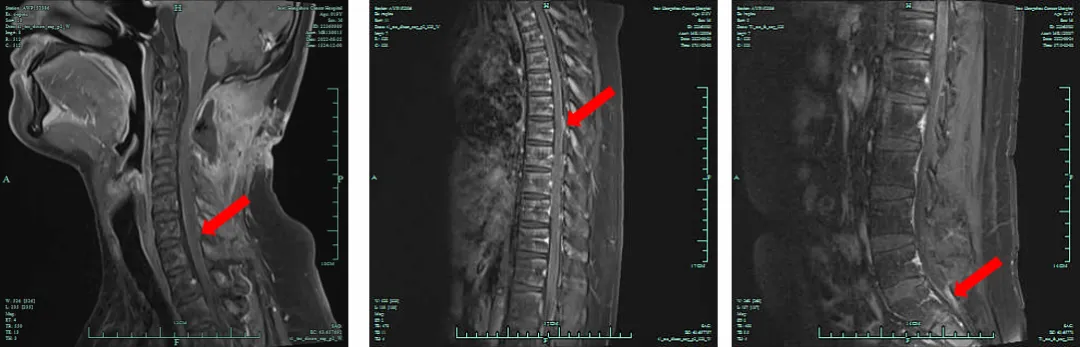

2022年9月15日,头颅MRI提示疾病稳定(SD)。

图4.维持化疗期间头颅MRI检查结果(2022.9.15)

2022年10月14日,行脊髓MRI检查,疗效评价SD。

图5.维持化疗期间脊髓MRI检查结果(2022.10.14)

2023年1月4日、1月6日,复查头颅MRI、脊髓MRI检查,疗效评价SD。

图6.维持化疗期间头颅MRI检查结果(2023.01.04)

图7.维持化疗期间脊髓MRI检查结果(2023.01.06)